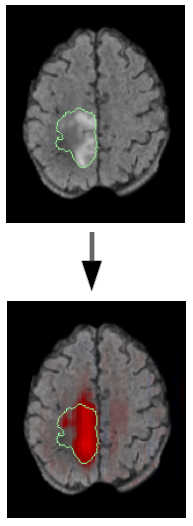

Des chercheur de CREATIS ont proposé une méthode d'apprentissage profond faiblement supervisée pour la classification (sain/pathologique) et la détection d'anomalies médicales. Elle contraint le modèle à prendre des décisions basées sur des marqueurs radiologiques, améliorant l'interprétabilité. Les résultats montrent une meilleure pertinence clinique et une supériorité en détection d'anomalies, notamment dans la segmentation des lésions de sclérose en plaques, par rapport aux méthodes de l'état de l'art.

En savoir plus